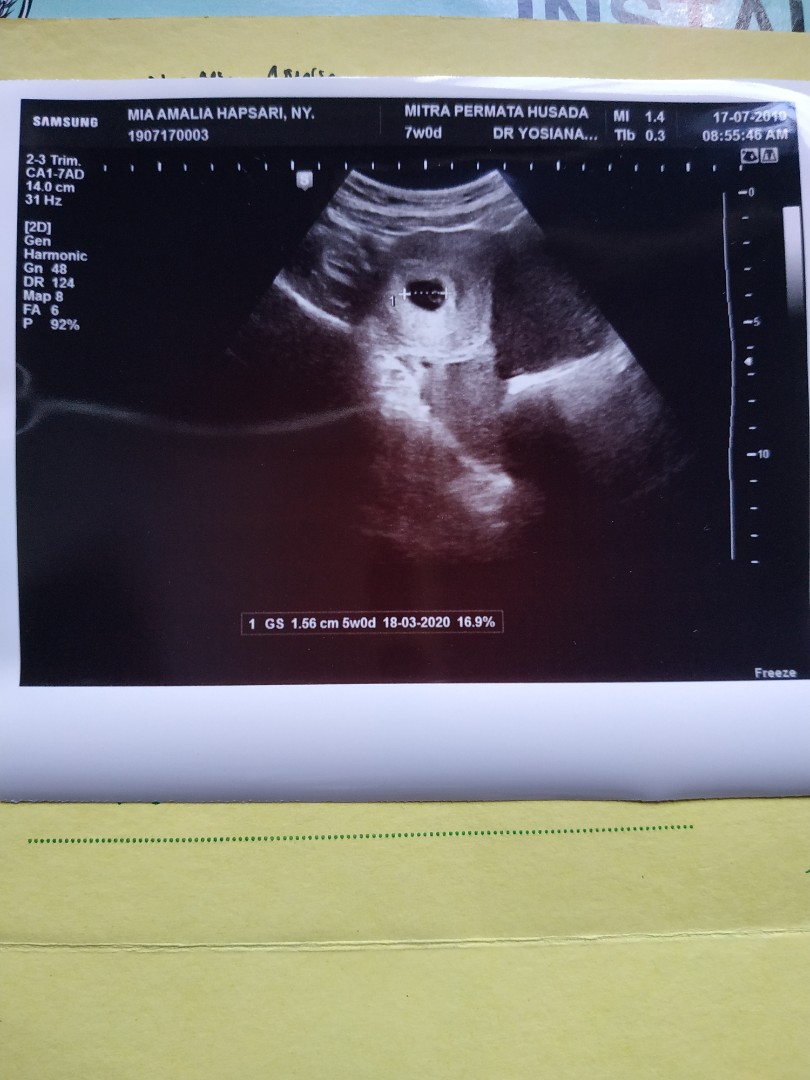

usg

Bun,usia 6w gambar usg nya kygini normal ga sih Bun?? Tadi dokternya bilang, ga berkembang masa?? Disuruh balik lagi seminggu selanjutnya untuk di usg lagi